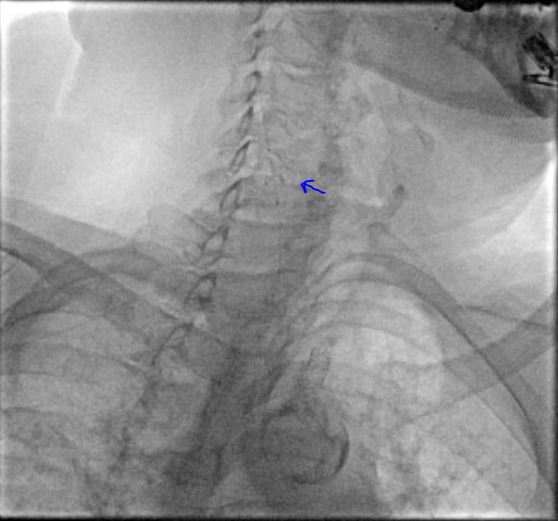

At this moment we elected to proceed with endovascular intervention through the radial access. Via right radial access, a long Runthrough wire (Terumo Interventional Systems) crossed the stenosis into the distal aorta, and we upgraded the sheath to 7F over both wires (BareWire and long Runthrough). We exchanged the long Runthrough wire with a Glidewire Advantage (Terumo Interventional Systems) via a TrailBlazer support catheter (Medtronic). We predilated with an 8-mm balloon and then an 8-mm x 29-mm Omnilink ballon-expandable stent (Abbott Cardiovascular) was successfully placed in the right innominate artery and deployed (Figure 3). Next, a pigtail catheter was advanced through the groin and angiography was performed, showing an under-expanded and malapposed mid to distal area of the stent (Figure 4), which was post-dilated with a 14-mm x 10-mm Armada balloon (Abbott Cardiovascular) (Figure 5), after which the filter was removed and a final aortogram showed good results with better apposition without complications (Figure 6).